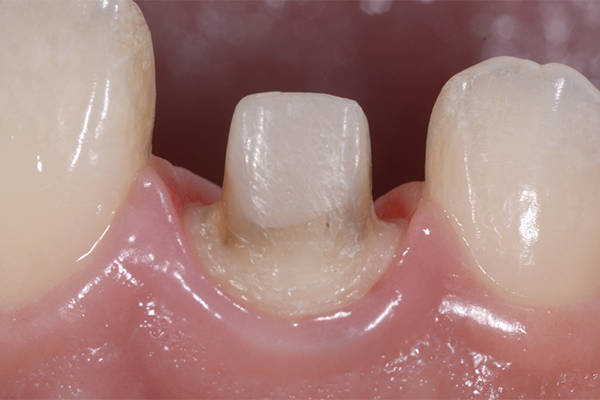

1.治療前

右上の一番真ん中の前歯に腫れやお痛みがあり来院されました。

一見きれいな冠で治療できているように見えます。